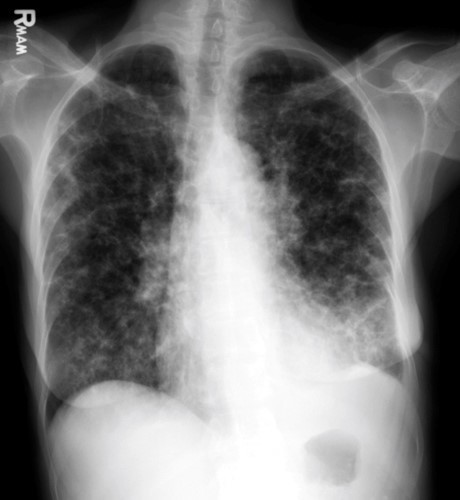

35yo female with history of heavy smoking and chronic lung disease

View

DX

View: PA

DX: CHF, diffuse pneumonia, interstitial lung disease